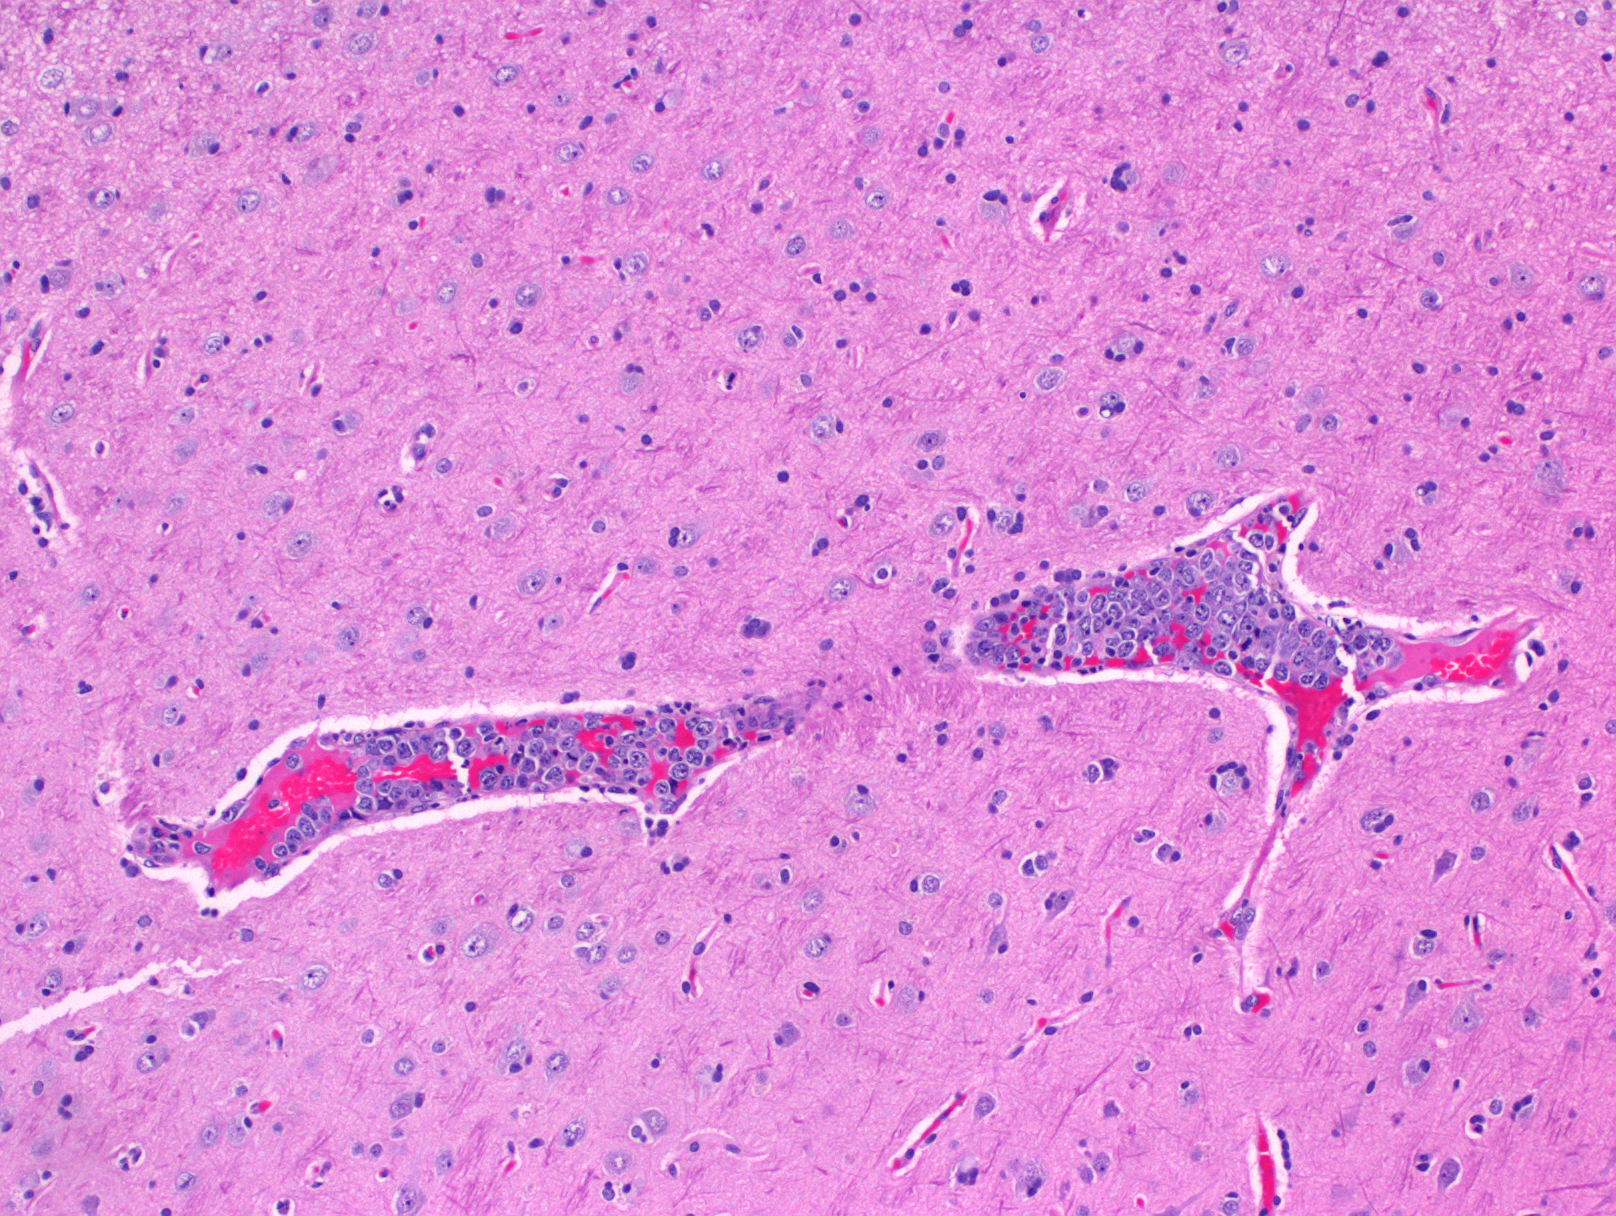

- 肿瘤淋巴细胞主要分布于小到中等血管腔内,或位于肝、脾(红髓)、骨髓的血窦内,可伴纤维蛋白血栓、出血、坏死。有时可见少量血管外瘤细胞。

- 肿瘤细胞大到中等,泡状染色质,核仁明显;有时可见粗大核染色质和不规则或锯齿状细胞核;有丝分裂像多见。